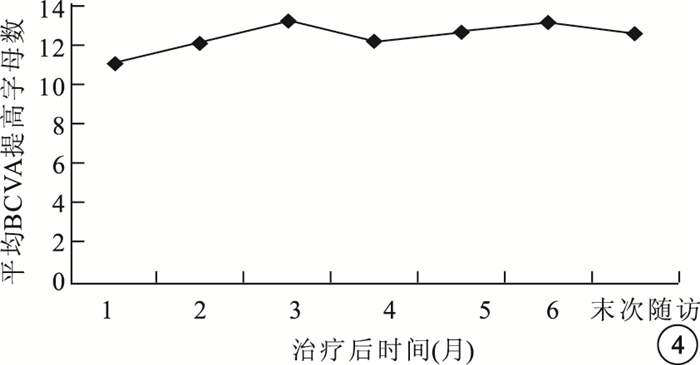

末次隨訪時,FFA、ICGA檢查發現,黃斑區CNV病灶滲漏消失(圖 6,7)6只眼,占30%;滲漏減輕11只眼,占55%;滲漏擴大3只眼,占15%。OCT檢查發現,所有患眼視網膜水腫消退,神經上皮脫離消失(圖 8),仍存在RPE脫離1只眼。

末次隨訪時,FFA、ICGA檢查發現,黃斑區CNV病灶滲漏消失(圖 6,7)6只眼,占30%;滲漏減輕11只眼,占55%;滲漏擴大3只眼,占15%。OCT檢查發現,所有患眼視網膜水腫消退,神經上皮脫離消失(圖 8),仍存在RPE脫離1只眼。